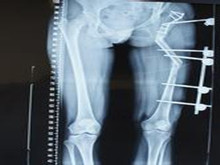

骨延伸是指拉伸成骨,即切割骨,保留软组织和血液供应,用专用牵引装置固定两端,采用...

X线平片